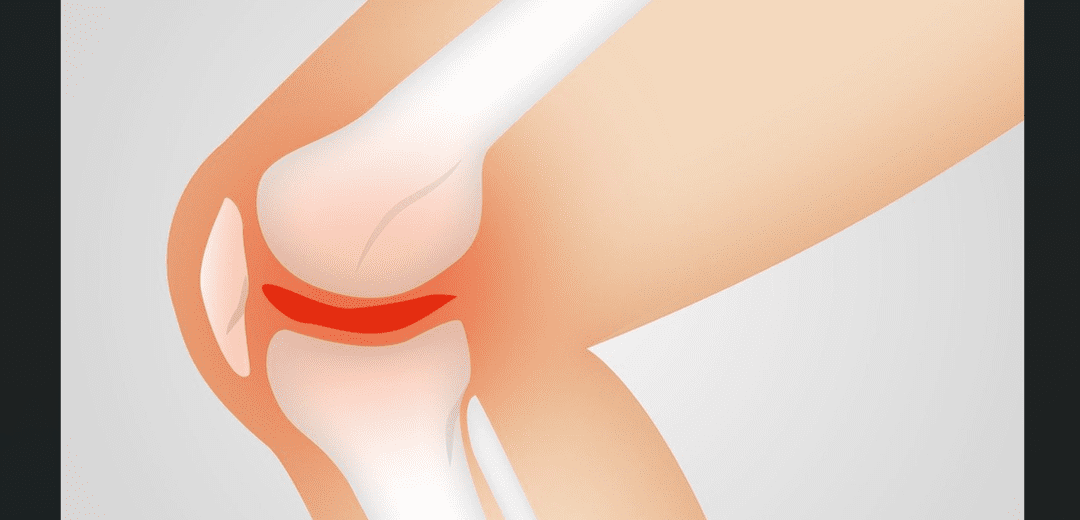

퇴행성 변화는 노화는 함께 발생하는 자연적인 과정으로, 관절 내부의 연골 파손과 변형이 주된 원인입니다. 나이 증가함에 따라 연골은 노화하고 손상되며, 이로 인해 관절 표면 간 마찰이 증가하여 통증을 유발합니다. 또한, 연골 파괴로 인해 관절 내부의 염증 반응이 발생할 수 있으며, 이는 통증과 뻐근함을 느낄 수 있습니다.